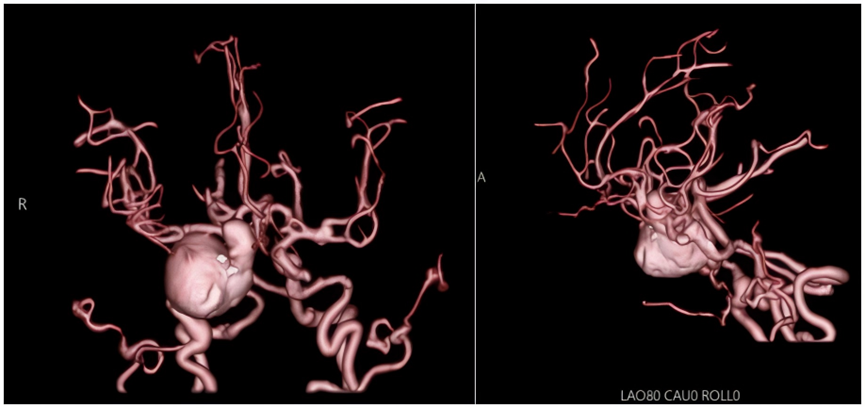

在当地医院检查后,结果令人心惊:头颅计算机体层摄影(CT)血管造影(CTA)显示其颅内存在多发动脉瘤!最凶险的一颗位于右侧颈内动脉,直径长达3厘米,紧邻着另一个超过1厘米的“邻居”;祸不单行,左侧颈内动脉上还潜伏着一个形状不规则的动脉瘤。三颗“不定时炸弹”深藏颅内,随时有破裂致命风险,这让陈阿婆和家人寝食难安,当地医院也深感棘手。经辗转,陈阿婆慕名来到仁济医院南院区,求助于颅脑肿瘤中心主任张晓华团队。

“经脑血管造影检查确诊,患者颅内共有3个高危动脉瘤:右侧是巨大型+大型的‘组合’,左侧则是不规则伴子结节的‘隐患’。”张晓华主任医师介绍道“尽管患者目前症状轻微,但3个动脉瘤随时都有破裂出血的风险,犹如定时炸弹一样。哪一颗一旦在血流的冲击下发生破裂,势必会造成颅内大出血,后果将是灾难性的,积极干预刻不容缓!”

图片

头颅CTA提示右侧颈内动脉C4-C6段多发动脉瘤,左侧颈内动脉C6段不规则动脉瘤

脑血管造影显示双侧颈内动脉多发动脉瘤